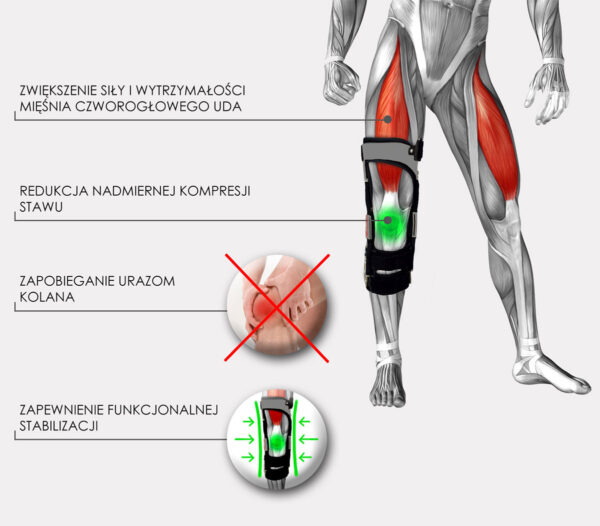

PRZEDNIO-TYLNA BIONICZNA ORTEZA KOLANA Z MECHANIZMEM SPRĘŻYNOWYM

RAPTOR BIONIC to coś więcej niż zwykła orteza ramowa kolana. Swoją innowacyjną bioniczną konstrukcję zawdzięcza zastosowaniu mechanizmu sprężynowego w zawiasach. Ma on na celu kumulację energii i przenoszenie obciążeń, wytwarzanych przez użytkownika w trakcie ruchu zgięciowego kolana, co znacząco odciąża staw kolanowy. W trakcie prostowania stawu, mechanizm wykorzystuje zmagazynowaną energię i wspomaga pracę prostowników kolana.

W rezultacie, orteza nie tylko stabilizuje staw kolanowy, ale dodatkowo zwiększa jego siłę i wytrzymałość.

ZALETY RAPTOR BIONIC: